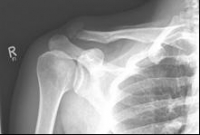

Schlüsselbein 2                  Schlüsselbein 3

Images: A lateral clavicle fracture was treated with a hook plate. The hook is fixed under the acromioclavicular, while screws anchor the plate in the collarbone.